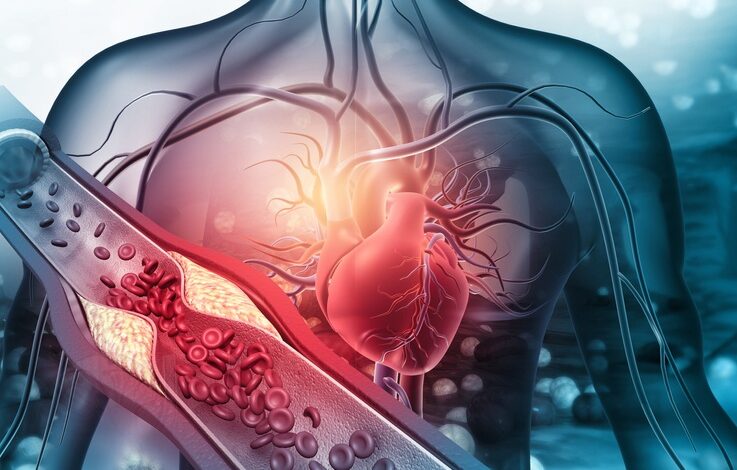

क्या युवाओं में अचानक मौतों का है कोरोना कनेक्शन?

अगर आप युवा हैं और कोरोना (Corona Virus) के घातक वायरस की चपेट में आ चुके हैं, तो आपको अपनी सेहत को लेकर काफी सतर्क रहने की जरूरत है। दरअसल सेहत से जुड़ी एक चौंकाने वाली रिपोर्ट सामने आई है। डॉक्टरों का कहना है कि जो लोग करोना वायरस की चपेट में आ चुके हैं, उन लोगों में अचानक हार्ट अटैक से मौत का खतरा सबसे ज्यादा है। ऐसे में मामलों में लगातार इजाफा हो रहा है। दिल्ली के कुछ अस्पतालों में 10 से 15% की बढ़ोतरी देखी गई है। यह चौंकाने वाली जानकारी हाल ही में एक अमेरिकी रिसर्च के बाद सामने आई है। रिसर्च के मुताबिक, कोरोना वायरस से पीड़ित हो चुके लोगों में कार्डियक अरेस्ट, स्ट्रोक का खतरा सबसे ज्यादा है। हालाकि भारत सरकार की ओर से इस बाबत कोई डेटा सार्वजनिक नहीं किया गया है।मैक्स अस्पताल, साकेत में कार्डियक विभाग के डायरेक्टर डॉ बलबीर सिंह ने बताया कि अचानक हार्ट अटैक से मरने वाले लोगों में 20 साल के युवा भी शामिल हैं। ऐसे मामलों में लगातार बढ़ोतरी हो रही है। हालांकि उन्होंने कहा कि इस मामले में अभी और रिसर्च और स्टडी की जरूरत है। कोरोना से पहले देश में 50 साल से कम आयु वर्ग के लोग 15 फीसदी लोग ही अचानक हार्ट अटैक की चपेट में आते थे, लेकिन अब 24 फीसदी तक ऐसे मामलों में बढ़ोतरी हो गई है।AIIMS के प्रोफेसर राकेश यादव के अनुसार, ऐसे मामलों के मात्रात्मक डेटा (Quantifiable Data) नहीं है, लेकिन ऐसे मामलों में कम से कम 10-15% की बढ़ोतरी देखी गई है। उन्होंने सुझाव दिया कि जो लोग कोविड से संक्रमित थे, उन्हें अपनी उम्र या फिटनेस की परवाह किए बिना सांस फूलने जैसे लक्षणों को नजरअंदाज नहीं करना चाहिए और तुरंत डॉक्टर से परामर्श लेना चाहिए। सीनियर कंसल्टेंट, कार्डियोलॉजी एंड इंटरवेंशनल कार्डियोलॉजी, नारायण हॉस्पिटल, डॉ. संजय कुमार चुग ने कहा कि युवाओं में कार्डियक अरेस्ट के कारण होने वाली मौतों में वृद्धि वेंट्रिकुलर फिब्रिलेशन से संबंधित असामान्यता के कारण हुई है। उन्होंने कहा, ‘ऐसे मामलों में दिल प्रभावी ढंग से धड़कना बंद कर देता है और अचानक से मौत हो जाती है। उन्होंने कहा, ‘कई युवा डॉक्टरों को एससीडी का सामना करना पड़ा है।’दिल्ली के धर्मशीला नारायण सुपरस्पेशलिटी अस्पताल के पल्मोनोलॉजिस्ट डॉ. नवनीत सूद ने कहा कि कुछ अध्ययनों में पाया गया है कि कोविड-19 के कई मामलों में सूजन के कारण शरीर के कुछ हिस्सों में क्लॉटिंग बढ़ गई है। कोविड मरीजों में ये रक्त के थक्के फेफड़े और हार्ट के अंदर हो सकते हैं। थक्के फेफड़ों में जा सकते हैं, जो शरीर खून के बहाव को प्रभावित कर सकते हैं और फेफड़ों की क्षमता को कम कर सकते हैं। एक्सपर्ट का कहना है कि चिंता की बात इसलिए है कि क्योंकि जिन लोगों की अचानक हार्ट अटैक से मौत हो रही है, उनकी ना कोई फैमिली हिस्ट्री है और 50 फीसदी मामलों में पेशंट्स धूम्रपान भी नहीं करते थे।